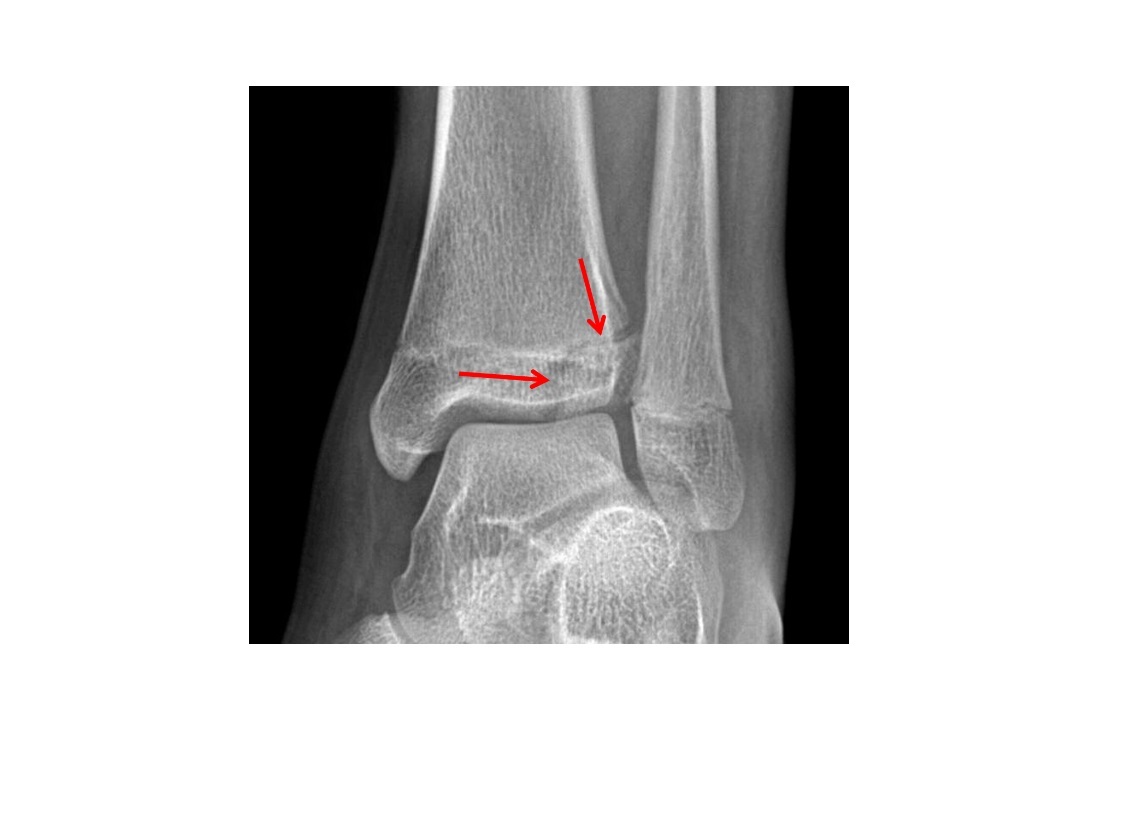

Tillaux fracture

Salter-Harris 3 = through the anterolateral distal tibial epiphysis